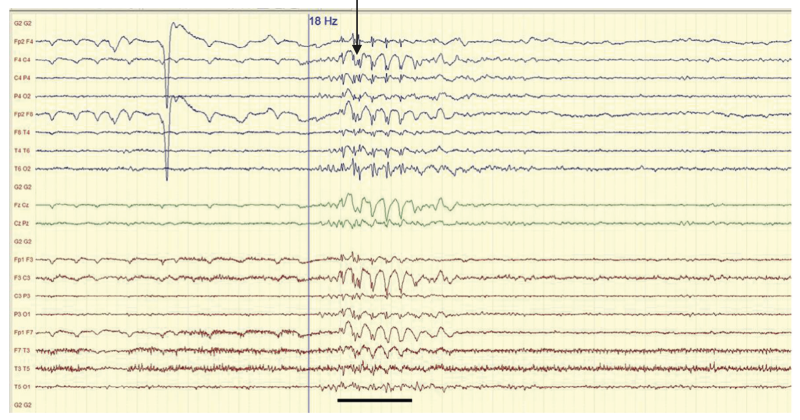

- EEG : bouffées de polypointes-ondes généralisées synchrones, favorisées par la stimulation lumineuse intermittente (figure 15.4).

Fig. 15.4.  Brève bouffée de polypointes-ondes généralisées synchrones.

Brève bouffée de polypointes-ondes généralisées synchrones.

(Source : CEN, 2019.)